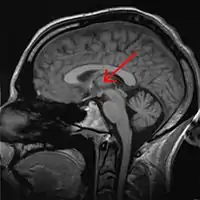

El núcleo reuniens es un componente del grupo nuclear medio del tálamo. En los mamíferos, está situado en la adhesión intertalámica (masa intermedia del tálamo).[1]

Tálamo separado mostrando los núcleos. Esquema.